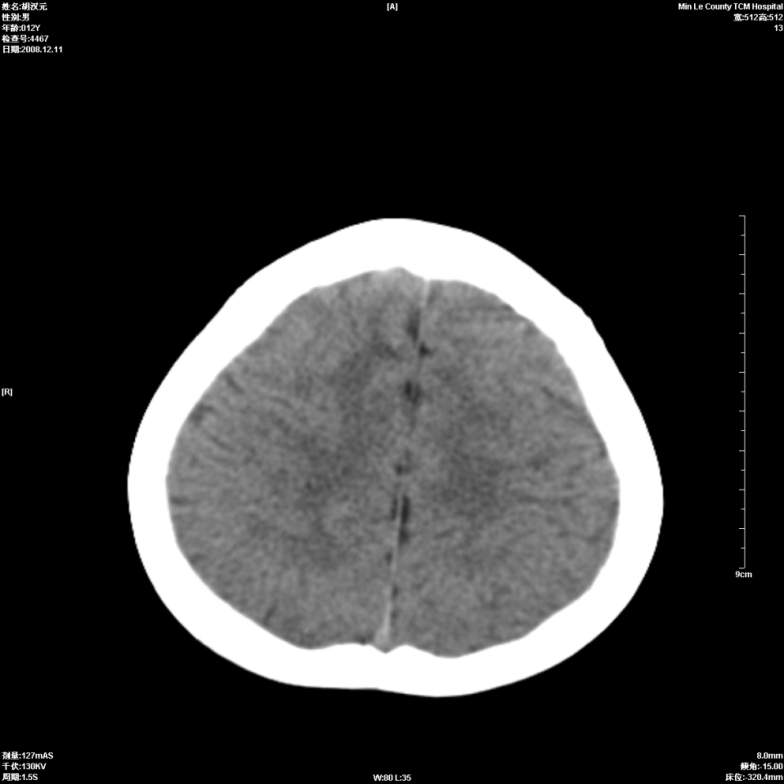

标题: PED1681:头疼发热约一周 [打印本页]

标题: PED1681:头疼发热约一周

颅脑未见确切异常。必要时进一步检查,如mri、脑脊液检查。

两侧顶部近灰质处白质密度降低,是否炎性改变

颅脑ct轴位平扫颅内未见明确异常;建议必要时复查或行进一步检查。

两侧顶部近灰质处白质密度降低,建议mri